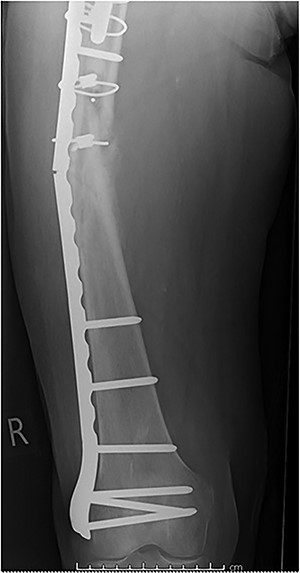

Case 2 (Figs 3–5): here difficulties were clearly encountered in achieving satisfactory reduction in the coronal plane. The screw immediately proximal to the fracture line is too close to the fracture.

Selecting a longer plate would have allowed proximal screws to sit more appropriately in order to reduce the risk of plate fatigue.